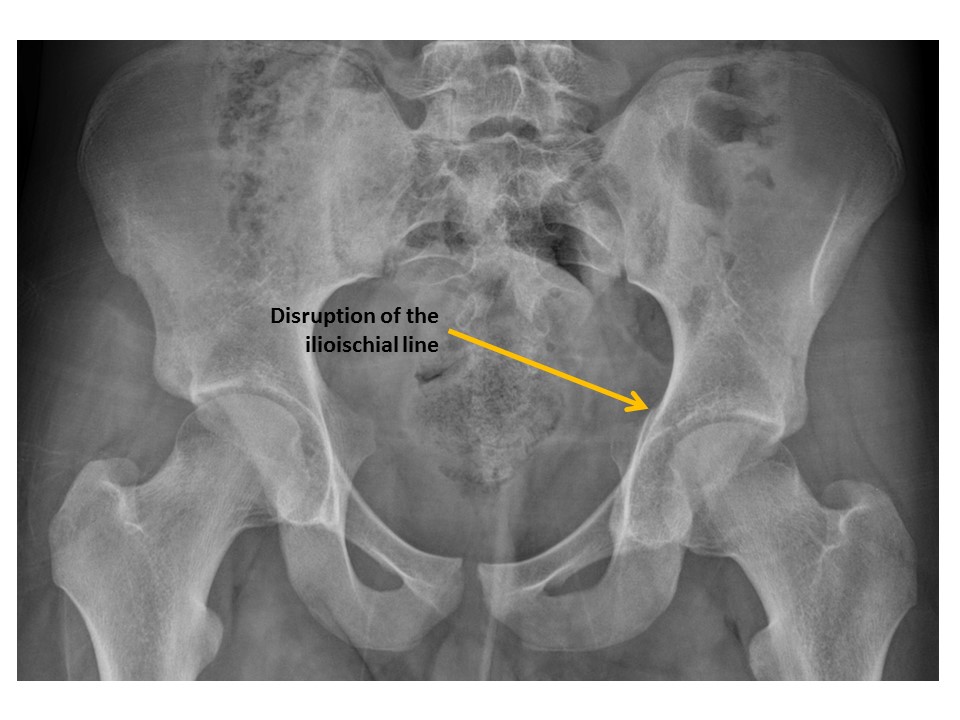

Ilioischial lines are disrupted. [Yes/No]